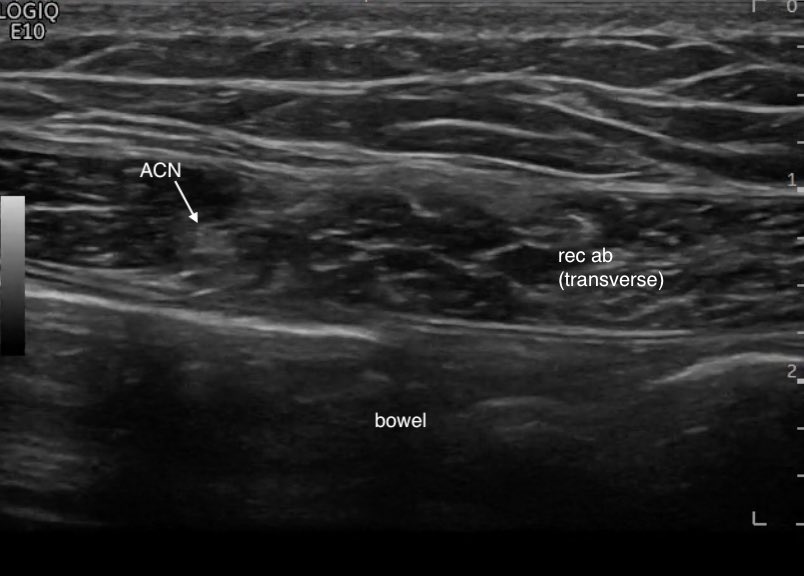

Dynamic ultrasound is performed, which shows reduced mobility of the sciatic nerve during knee and hip extension (comparative video of normal neural mobility: facebook.com/watch/?v=49781…).

The great utility of ultrasound is the assessment of the mobility of the sciatic nerve during neurodynamic exercises, which in cases where it is decreased compared to the contralateral nerve, can be used as a secondary sign for the diagnosis of DGS.